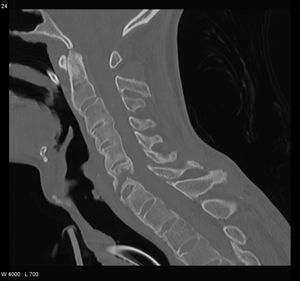

| An ankylosing spine in which the vertebrae become fused together. | |

التهاب الفقار المقسط أو اللاصق Ankylosing spondylitis باليونانيةankylos, stiff; spondylos, vertebrae), تسمى قديماًBekhterev's disease, Bekhterev syndrome, و Marie-Strümpell disease هو نوع من التهاب المفصل في العمود الفقري. وهو يسبب تورماً بين الفقرات، والفقرات هي الأجزاء الأسطوانية التي تكون العمود الفقري، كما يسبب تورماً في المفاصل بين العمود الفقري والحوض. إن التهاب الفقار المقسط أو اللاصق هو أحد أمراض المناعة الذاتية. إن الجهاز المناعي المسؤول عن حماية الجسم من العدوى يقوم بمهاجمة أنسجة الجسم نفسها في حالة أمراض المناعة الذاتية. ويكون التهاب الفقار اللاصق أكثر انتشاراً وخطورة عند الرجال. وكثيراً ما يكون مرضاً ينتقل عن طريق الوراثة.[1]

ومن أعراضه المبكرة ألم الظهر والتيبس. وهي تبدأ غالباً في مرحلة المراهقة المتأخرة أو أوائل البلوغ. ومع مرور الوقت يمكن لالتهاب الفقار اللاصق أن يؤدي إلى التحام الفقرات مما يقيد حركتها. يمكن أن تتفاقم الأعراض كما يمكن أن تتراجع أو تختفي تماماً. إن هذا المرض غير قابل للشفاء، لكن الأدوية يمكن أن تهدئ الألم والتورم والأعراض الأخرى. ويمكن أن تكون التمارين الرياضية مفيدة أيضاً.

يحدث التهاب العنبية الأمامي في حوالي ربع المرضى، ويتظاهر بألم واحمرار وخوف من الضياء، وتكون هذه الإصابة نوبية، وحيدة أو ثنائية الجانب. يبدي الفحص السريري نقصاً في حركية العمود الفقري، مع فقد تام أو جزئي للقعس القطني الفيزبولوجي، وزيادة في الحدب الظهري. أما المظاهر المتأخرة فتشمل تحدد حركة جدار الصدر في الشهيق العميق (أقل من 2.5 سم) مع انحناء تدريجي، وثبات العمود الفقري والرأس في وضعية العطف. ويمشى المريض جاراً قدميه Shuffling Gait مع تفاوت شدة إصابة المفاصل المحيطة.[2]